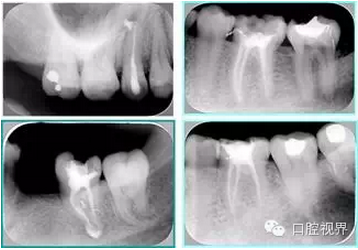

6. 術(shù)后 X 線片

術(shù)后 X 線片用來評定根管充填 長度、致密度(管壁清晰、側(cè)枝)等指標(biāo)。

左圖為根管充填術(shù)后 X 線片。圖中可見,根管充填較好。右下圖有白色小點,為側(cè)方加壓導(dǎo)致糊劑擠出所致,表明根管充填比較致密。

致密、恰到好處的充填可去除干凈根管里感染灶,機體逐漸恢復(fù)。

多根牙時候需進行偏移投照,正位投照無法說明具體哪根牙根管充填效果。